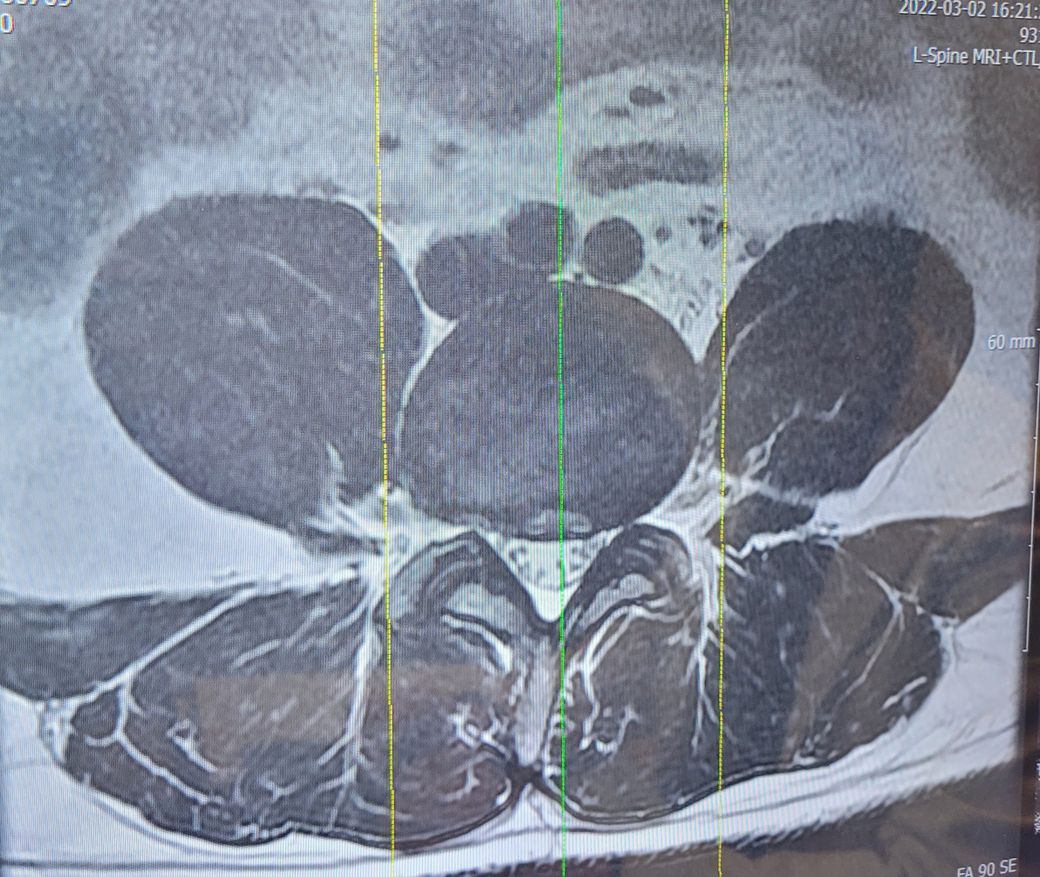

오늘 MRI를 찍었는데 4,5번 디스크가 나와서 신경을 눌려서 그렇다고 수술을 하라고 하던데...

• 2번 째 사진

MRI상 디스크 탈출로 인한 증상으로 보입니다.